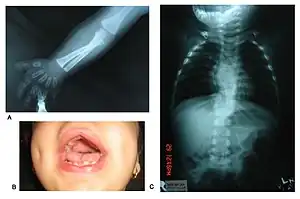

Patients suffer from dwarfism, short lower arms, small feet, and small hands. Fingers and toes may also be abnormally short and laterally or medially bent. The thumb may be displaced and some patients, notably in Turkey, experience ectrodactyly.[1] All patients often suffer from vertebral segmentation abnormalities. Those with the dominant variant have, at most, a single butterfly vertebra.[2] Those with the recessive form, however, may suffer from hemivertebrae, vertebral fusion, and rib anomalies. Some cases resemble Jarcho-Levin syndrome or spondylocostal dysostosis.[1]

Genital defects characteristically seen in males include a micropenis with a normally developed scrotum and testes. Sometimes, testicles may be undescended, or the patient may suffer from hypospadias.[2] Female genital defects may include a reduced size clitoris and underdeveloped labia minora. Infrequently, the labia majora may also be underdeveloped.[2] Some research has shown that females may experience vaginal atresia or haematocolpos.[3]

| Upper lip | Tented upper lip | Normal upper lip |